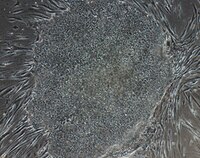

EMD Millipore’s Simplicon® RNA Reprogramming Kit is a safe and efficient method to generate integration free, virus-free human iPS cell using a single transfection step of self-replicating synthetic RNA for Oct4, Klf4, Sox2, Glis1 and c-Myc.

More>> EMD Millipore’s Simplicon® RNA Reprogramming Kit is a safe and efficient method to generate integration free, virus-free human iPS cell using a single transfection step of self-replicating synthetic RNA for Oct4, Klf4, Sox2, Glis1 and c-Myc. Less<<Productos recomendados